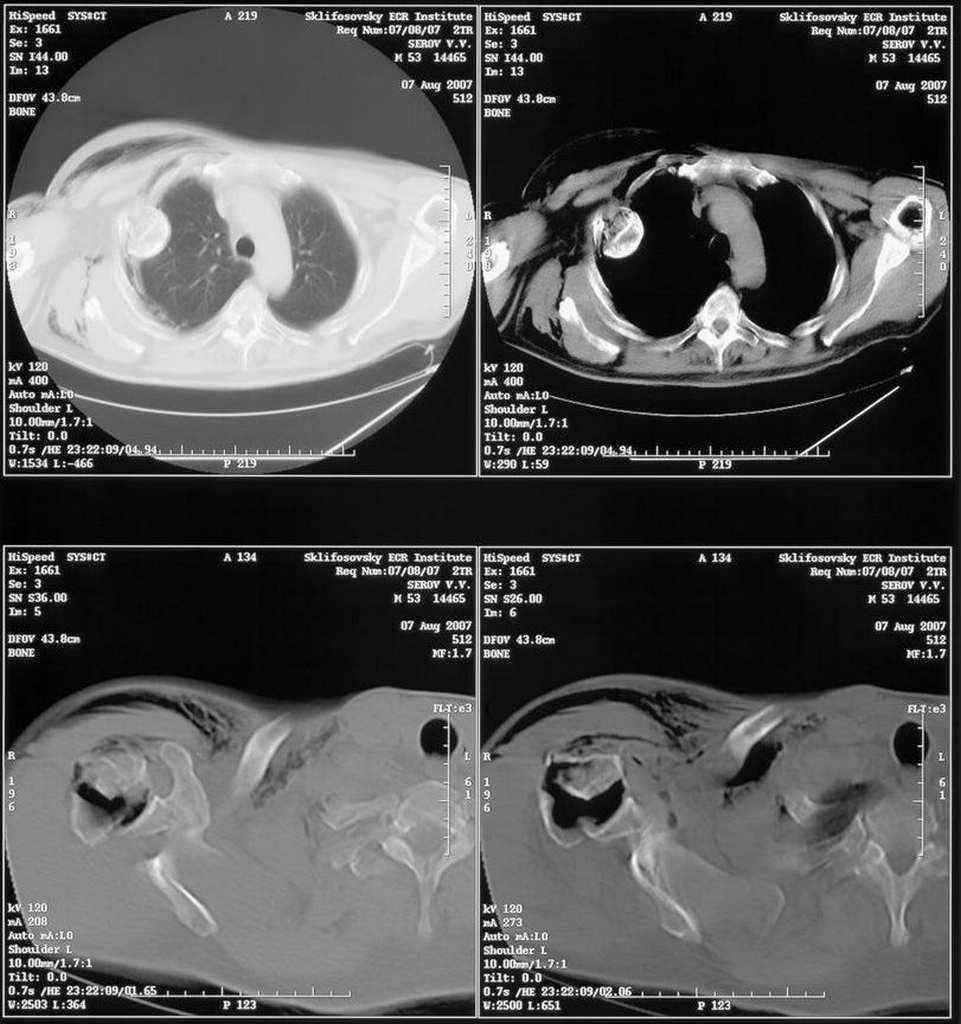

Правый плечевой сустав умеренно деформирован. По внутренней поверхности плеча имеется кровоподтек. При пальпации плечевого сустава имеется умеренная болезненность. Активные и пассивные движения болезненные. Снижена чувствительность по тыльной поверхности пальцев кисти и отсутствует активное разгибание кисти и пальцев. Имеется подкожная эмфизема шеи, верхней половины грудной клетки (рис 1, 2). На рентгенограмме: оскольчатый перелом головки плечевой кости со значительным смещением, перелом 2-3 ребер справа, тканевая эмфизема (рис 3). КТ при поступлении: перелом головки плечевой кости в области анатомической шейки со смещением отломка головки в грудную полость, правосторонний гидроторакс, перелом 2-3-4 ребер справа. (рис 4). Через двое суток после поступления выполнена операция: атипичная торакотомия, эвакуация свернувшегося гемоторакса, удаление инородного тела (головки плечевой кости) из плевральной полости (при этом выявлено имеющееся повреждение париетального и висцерального листков плевры) (рис. 5), дренирование плевральной полости, замещение проксимального конца плечевой кости спейсером из костного цемента с антибиотиком (рис. 6). Послеоперационный период протекал гладко. При контрольной рентгенографии положение спейсера удовлетворительное (рис. 7, 8). Дренаж из плевральной полости удален через 3 суток после вмешательства. Послеоперационная рана зажила первичным натяжением. Через 12 дней после операции больной выписан на амбулаторное лечение.